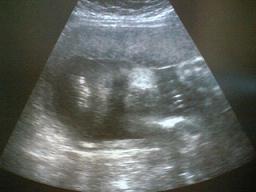

2007年5月31日撮影。

28w3d

BPD(児頭大横径)=7.38センチ

FTA(躯幹面積)=39.83平方センチ

FL(大腿骨長)=4.72センチ

推定体重=1170グラム

左の写真はわかりにくいので右の写真で図解!

今回からパーツごとにしかモニターに表示されなくなってしまいました!

顔もモニターいっぱいですw

気持ち少なめだけど週数相当の体重でした。

それにしても今回の写真は先生撮るの下手かも!><

もっとかわいい顔してるときがあったのになぁ・・・これはちょっと怖いw

ちなみに今回の写真は右が体になっていて、黒い部分が目、その右側に鼻と口がみえます^^

その顔の下に見えるのは手のようですw